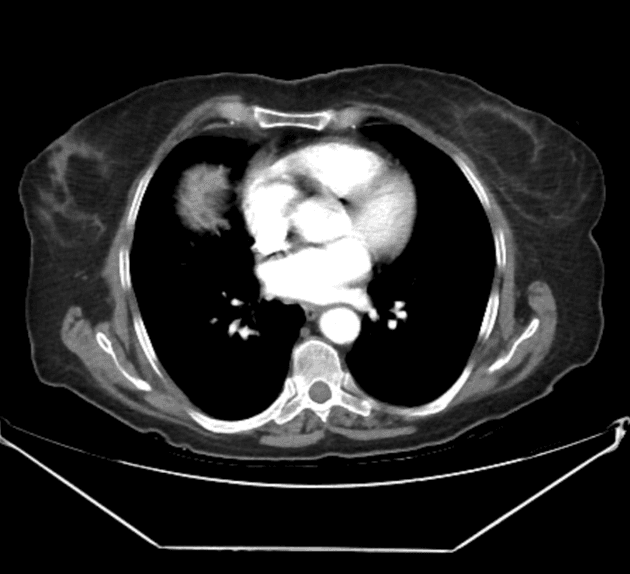

- Các dấu hiệu trên CT tương tự như MRI với đáy túi mật căng giãn, dịch quanh túi mật (pericholecystic fluid) và thâm nhiễm mỡ (fat stranding).

- Thành túi mật bắt thuốc kém (poorly enhancing) ở vùng đáy với các thành phần trong lòng tăng tỷ trọng (hyperattenuating) gợi ý xuất huyết trong lòng (intraluminal hemorrhage).

- Thấy dấu hiệu "mỏ chim" ("beak" sign) với sự xoắn vặn của thành túi mật. Túi mật đoạn gần bị xẹp.

- Tiền sử cắt đại tràng phải (right hemicolectomy). Có ít dịch tự do quanh gan (perihepatic free fluid).

Một dấu hiệu hình ảnh đáng chú ý trong trường hợp xoắn túi mật này là sự hiện diện của "bóng mờ T2" (T2 shading) của các thành phần trong lòng đáy túi mật. Điều này có khả năng đại diện cho xuất huyết trong lòng hoặc dịch phức hợp. Dấu hiệu này tương ứng với dịch tăng tỷ trọng trên CT. Các thành phần trong lòng túi mật ở đoạn gần điểm xoắn cho thấy cường độ tín hiệu dịch đơn thuần trên MRI và tỷ trọng dịch trên CT. Dấu hiệu "mỏ chim" (beak sign) của sự thắt hẹp lòng túi mật đột ngột và động mạch túi mật xoắn vặn (whorled cystic artery) cũng được ghi nhận tại điểm xoắn.